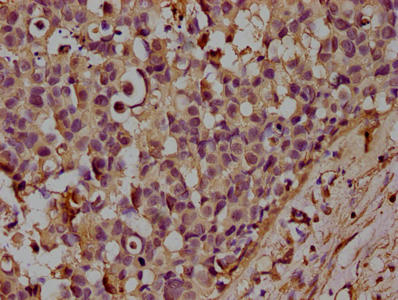

100 μg - FOXP3 antibody [orb34127]Featured

ELISA, ICC, IF, IHC-P, WB

Human, Mouse, Rat

Rabbit

Polyclonal

Unconjugated

100 μg - OPG antibody [orb247239]Featured